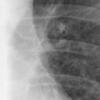

Aortic nipple

Date: 01/12/2015

Views: 3187

Aortic nipple PA and CT

Date: 01/06/2018

Views: 3165